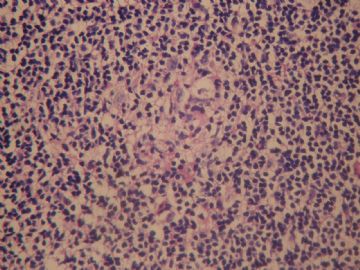

• 左颈淋巴结肿大图3

图3

老年女性,全身多发 淋巴结肿大,图1见深染区和浅染区,图2 和3见生发中心血管植入,呈蚊香样结构,图4,5见组织细胞增生,未见吞噬现象,淋巴结髓索和窦境界存在,见滤泡结构,首先考虑淋巴结反应性增生病变(窦性增生),但要排除castlamen病可能

老年女性,全身多发 淋巴结肿大,图1见深染区和浅染区,图2 和3见生发中心血管植入,呈蚊香样结构,图4,5见组织细胞增生,未见吞噬现象,淋巴结髓索和窦境界存在,见滤泡结构,首先考虑淋巴结反应性增生病变(窦性增生),但要排除castlamen病可能,浆细胞不明显